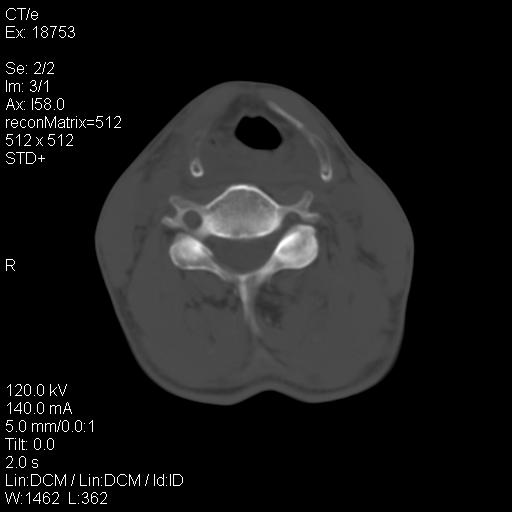

标题: CT21693:男 58岁 右侧咽部疼她2天余 PE:右侧扁桃体肿大 压痛 [打印本页]

标题: CT21693:男 58岁 右侧咽部疼她2天余 PE:右侧扁桃体肿大 压痛

右化脓性扁桃体炎症伴咽后壁脓肿形成.